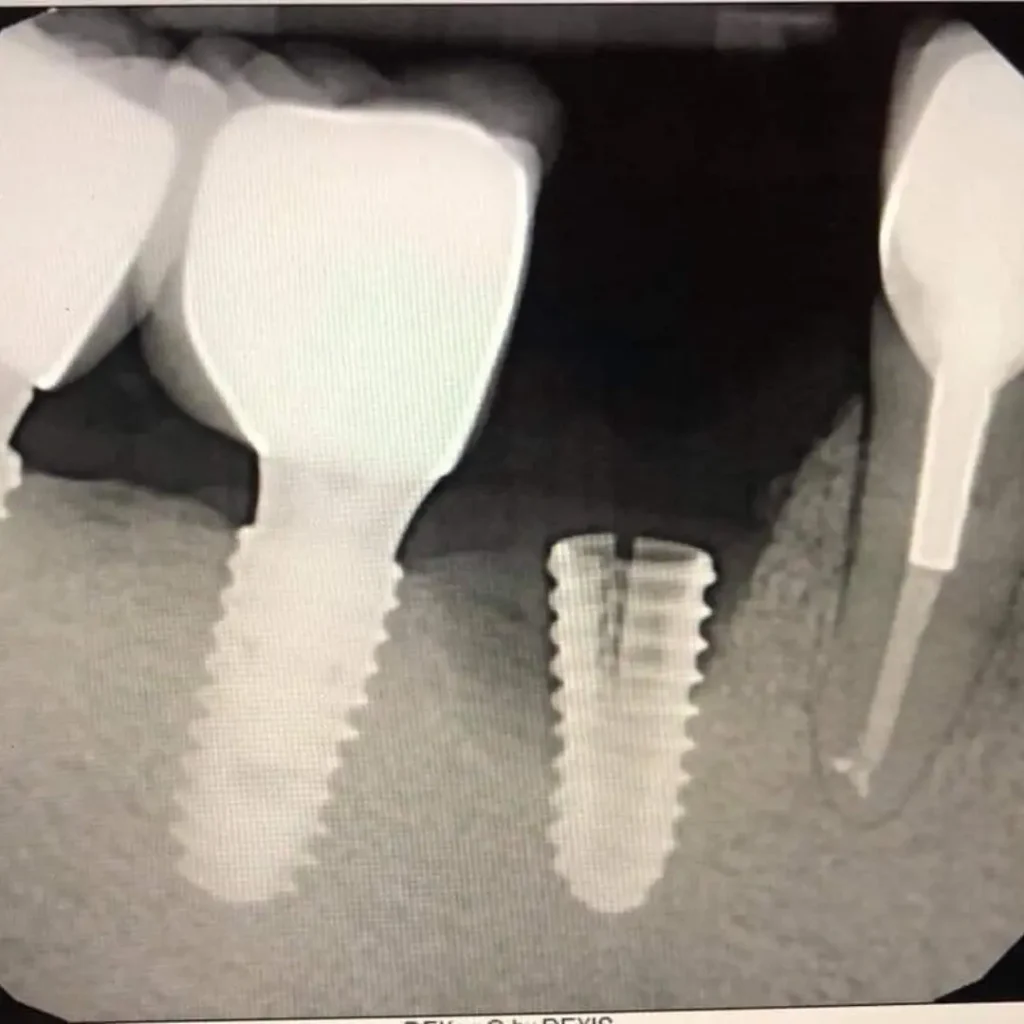

What if I don’t have enough bone for an implant?

In cases where there’s bone loss, a bone graft may be required to rebuild the area before the dental implant procedure. Our specialists will evaluate your condition and develop a personalized treatment plan.

What types of dental implants do you offer?

We provide several types of dental implants, including single-tooth implants, implant supported bridges, and full-arch restorations. For emergencies, we assess what’s best depending on your situation and oral health.

How does an implant differ from a dental bridge?

A dental implant replaces both the natural tooth and its tooth root, making it more stable and long-lasting. A dental bridge relies on adjacent teeth for support. We’ll help you decide which option suits your case best.